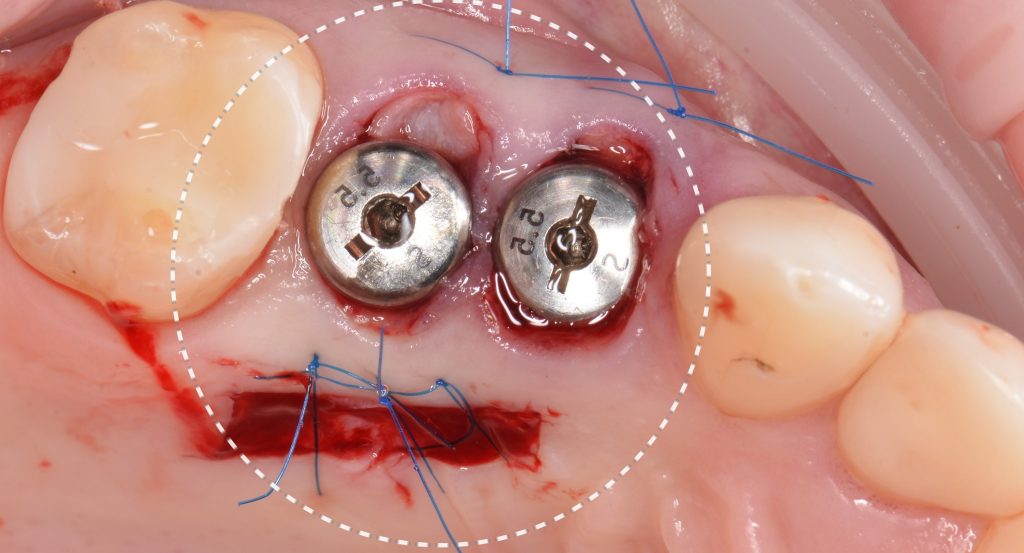

The decision has been made to perform immediate implant placement to replace teeth 24 (Universal 12) and 25 (Universal 13).The optimal position of the future implant is planned by starting with intraoral scanning and importing digital models into the Diagnocat STL module

A template for guided implant surgery was planned and manufactured based on these digital models for the replacement of teeth 24 (Universal 12) and 25 (Universal 13)